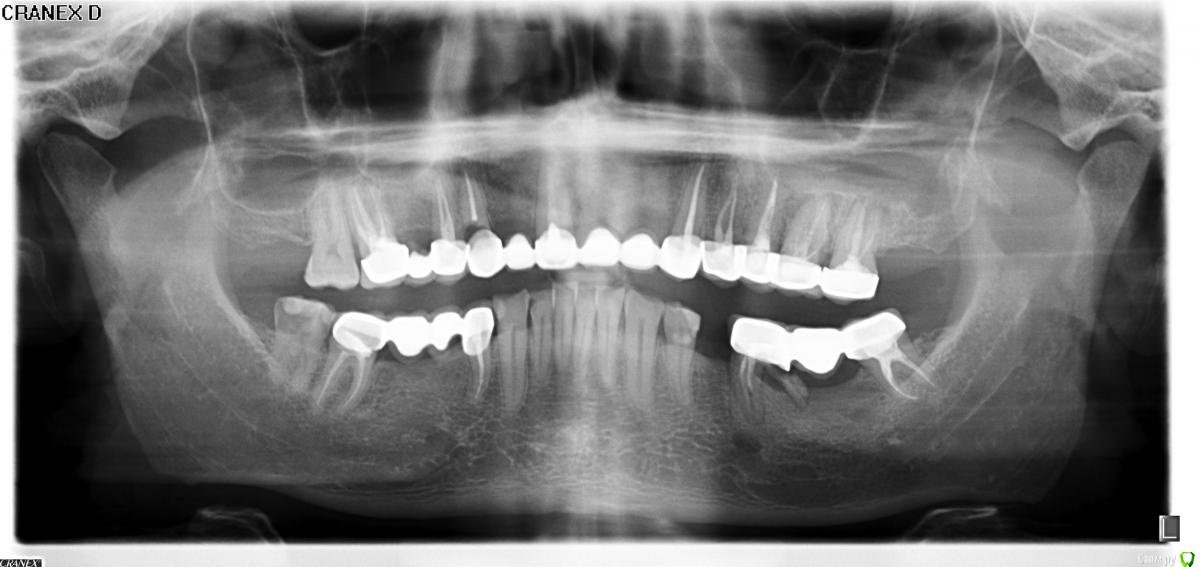

Капитальный ремонт мостов.

13- кариес корня, недопломб верхушк 3мм, пустоты в канале

26, 27 - кеста 4-5 мм

36,

48

все приговорили удалять!

16, 17 - лечить

Какие будут мнения? В основном интересуют 26, 27.

Потом предполагается мост 17-16-14-11-23-24-25. Не великоват ли? :)

Импланты 35,36,37,26,27

Почему бы не поставить импланты в позицию 15,13,12,21,22,26,27 и сделать все коронки одиночками. 35,36,37 импланты тоже с одиночками либо 35,37 и мост на имплантах. Внизу обошлись бы без врем съемного чтобы не было излишней атрофии. Вверху врем мост тогда уж на 16,14,11,23,24,25.